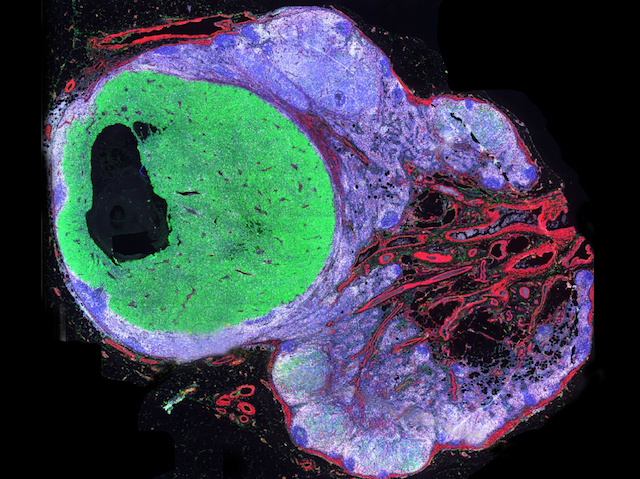

Imagine looking at a map but only seeing the motorways, or fields, or rivers. You wouldn’t be getting the whole picture. A similar problem arises when looking at tissue biopsies from patients. With cancer tissue biopsies, spotting changes in multiple proteins often means more appropriate treatment can be given. Researchers now present a technique called tissue-based cyclic immunofluorescence (t-CyCIF), which images multiple proteins at high resolution. Human tissue biopsies were treated with fluorescently tagged antibodies that bound a specific protein. Each biopsy was imaged, the fluorescence then deactivated and the process repeated again for different proteins. Stitching together the images revealed a more complete picture of the tissue. In the case of metastatic skin cancer (pictured), the team simultaneously looked at proteins marking out cancer cells (green), immune cells (white) and connective tissue (red). With this approach researchers can more easily uncover changes that occur in cancer for more personalised treatments.